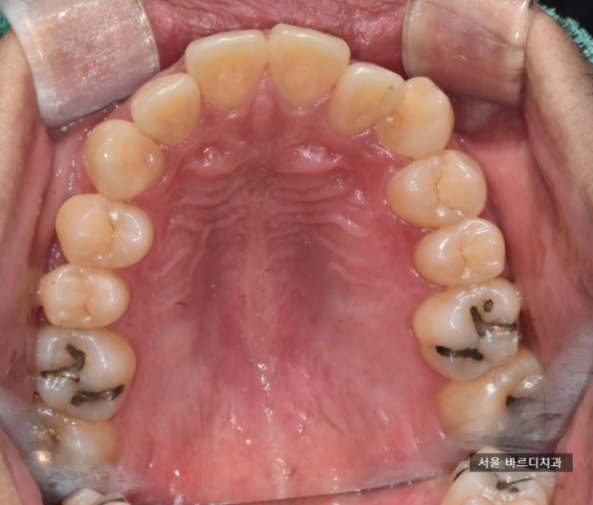

왜이렇게 사진을 많이 찍나 생각하실 겁니다.

x-ray 로는 설명이 쉽지않아

치아 사진으로 설명을 진행합니다.

치료 전, 후 비교 사진을 찍어서 보여드려요!!